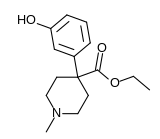

4-Phenylpiperidines

Pethidines (meperidines)

- Hydroxypethidine (bemidone)

Structures